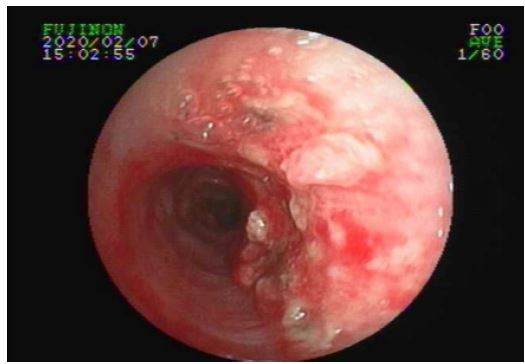

Figure 3: Reexamination of tracheoscopy indicated that the burn site of the original new organism was completely repaired.

The tumor was removed by argon plasma coagulation and biopsy forceps. On February 7, 2020, reexamination of bronchoscope indicated that the burn site of the original new organism was completely repaired (Figure 3).